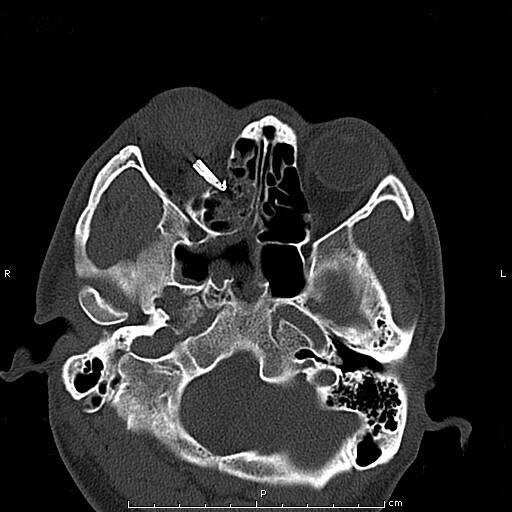

患者青年男性,因“右眼被鋼筆戳傷2小時余”入院,眼科查體:視力:右無光感,左0.4。眼壓:右不能檢查,左正常。右眼上瞼紅腫,鋼筆自顳上方眼瞼刺入,末端位置不詳,睜眼困難;結(jié)膜充血、水腫,角膜尚清,前房積血,余眼內(nèi)結(jié)構(gòu)窺不入。左眼未見明顯異常。入院后完善眼眶CT檢查,印象:右眼眶異物并右眼球破裂傷、眶內(nèi)壁骨折,異物嵌頓于眶壁。鋼筆內(nèi)含墨水,傷情重且復(fù)雜。